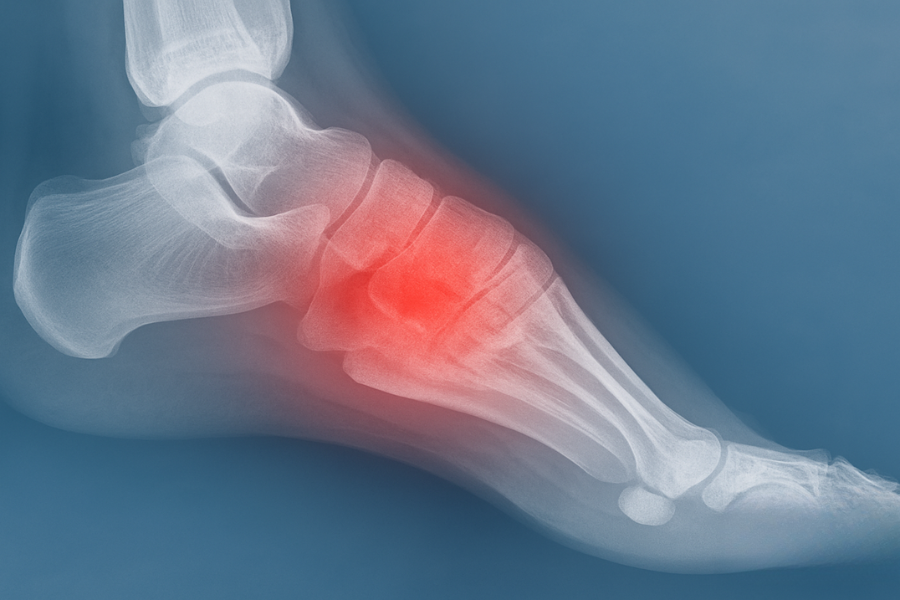

A diagnosis is crafted through a thorough evaluation by a foot and ankle surgeon, which includes a review of medical history and a physical examination of the foot. To definitively exclude fractures, X-rays are routinely performed, with the possibility of other imaging techniques being employed to ensure an accurate diagnosis.